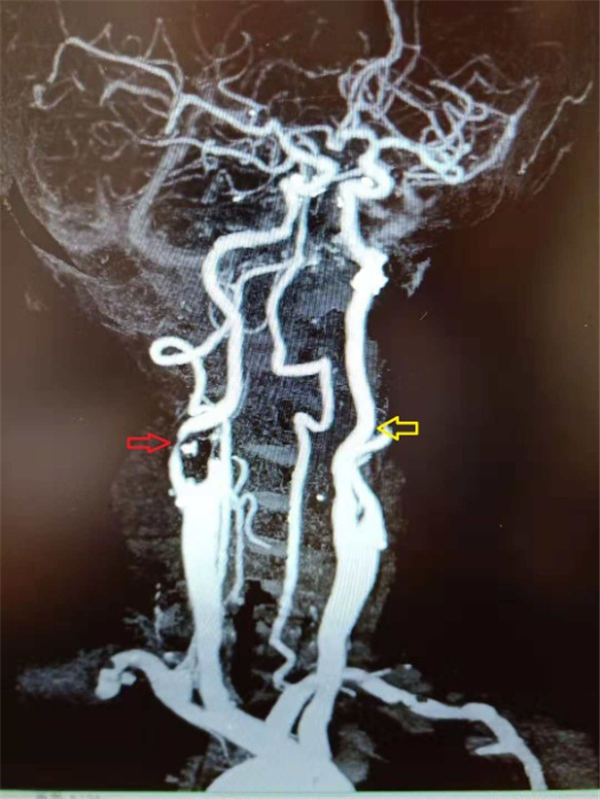

当天,老杜就顺利入住北京燕化医院,第三天就安排了介入手术:在右侧腹股沟局麻之后,穿刺股动脉插管到主动脉,再选择到右侧颈动脉造影,可见右侧颈内动脉重度狭窄、几近闭塞(上图红色箭头)。

确定狭窄部位之后,在微导丝的引导之下,小心的将保护伞(上图红色箭头之间)置于狭窄段远端,以阻拦可能脱落的斑块,避免术中脑梗塞的发生,手术结束之后再将保护伞回收。